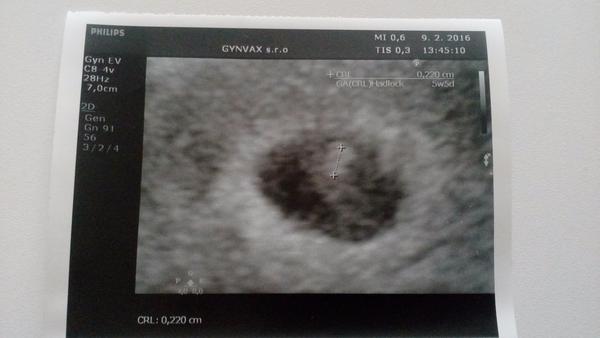

@niiik baby tak aj ja uz som bola u dr. Prave idem odtial 🙂 a jaaa budem maminkaaaa 🙂 aj som si dala spravit foto, aj ked take este nijake ;) uz aj srdiecko bolo vidno 🙂

@eva2809 budem drzat 🙂 hned pis ked pojdes odtial 🙂 mne najskor nechcel dat foto,vraj este je skoro,ale ja som si vyprosila 🙂

@luciferkax no ja som tiez skoro zabudla, a on sa aj najskor branil a nechcel dat foto 😀 ale ja som sa nenechala a uz ked som skoro odchadzala tak ze dobre vytlaci :D

@eva2809 no ja som platila 3 eura, ale to ma asi kazdy lekar inak, aspon si myslim 🙂 no nechcel dat,vraj je este skoro, a vraj budu este krajsie fotky 😀 no nedala som sa 😀